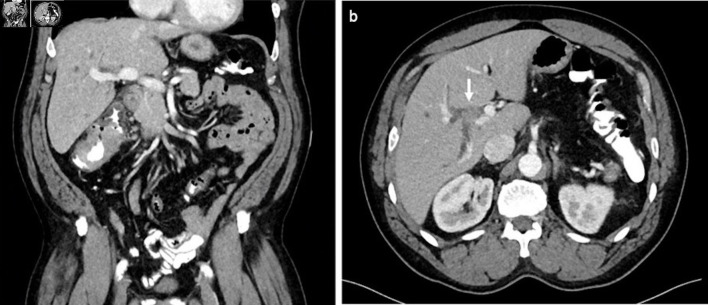

在极少数情况下,恶性胆道梗阻可能源于远处原发肿瘤转移到胆管。由于胆管转移瘤在临床和影像学上可能与胆管癌等原发性胆道肿瘤相似,因此这种现象往往给诊断带来挑战。我们介绍了一例独特的结直肠腺癌患者单发同步导管内胆管转移导致胆道梗阻的病例。患者最初被新诊断为肝曲处结肠癌,横断面影像学检查发现导管内肿块导致胆道梗阻。最初,导管内病变的性质并不确定,但通过组织病理学检查,最终确诊为转移性结直肠腺癌。该病例强调了区分转移性胆道梗阻和原发性胆道肿瘤的难度,并突出了在胆道肿块的非典型表现中考虑转移性疾病的重要性。我们讨论了有助于区分导管内结直肠腺癌转移瘤和原发性胆道肿瘤的几个关键放射学和组织病理学特征。

Malignant biliary obstruction can, in rare cases, arise from metastases to the biliary tree from distant primary tumors. This phenomenon often poses a diagnostic challenge, as bile duct metastases may clinically and radiologically mimic primary biliary tumors, such as cholangiocarcinoma. We present a unique case of solitary, synchronous intraductal biliary metastasis in a patient with colorectal adenocarcinoma that led to biliary obstruction. The patient initially presented with a new diagnosis of colon cancer at the hepatic flexure and was found, on cross-sectional imaging, to have biliary obstruction due to an intraductal mass. Initially, the nature of the intraductal lesion was uncertain; however, it was ultimately confirmed through histopathological examination to be metastatic colorectal adenocarcinoma. This case underscores the difficulty of distinguishing metastatic biliary obstruction from primary biliary tumors and highlights the importance of considering metastatic disease in atypical presentations of biliary masses. We discuss several key radiologic and histopathological features that may help differentiate intraductal colorectal adenocarcinoma metastases from primary biliary tumors.